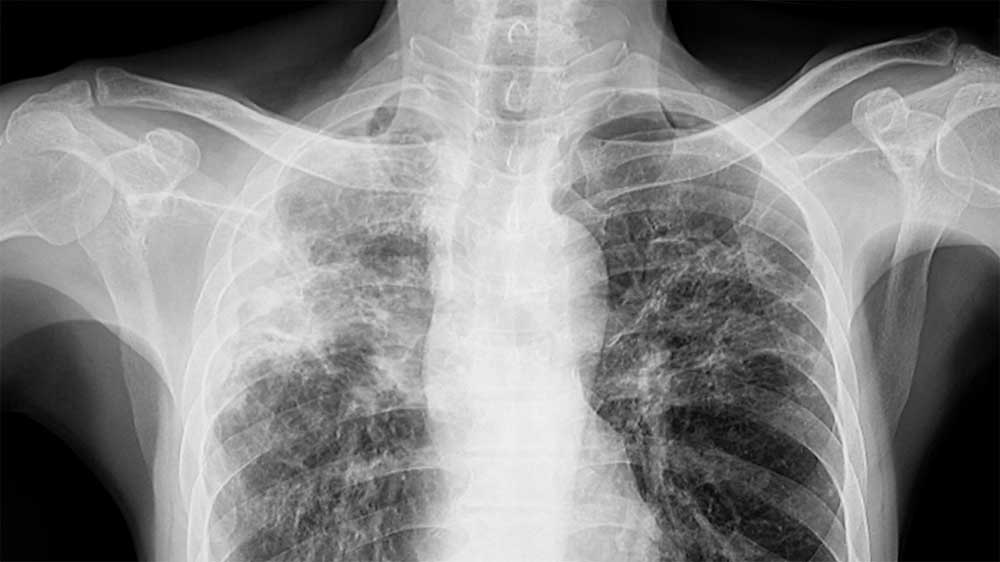

“En el curso hay 30 alumnos. Lo que vamos a hacer es lo que se hace siempre en estos casos: una placa de tórax y una prueba de Mantoux (PPD), que es un test para detectar si una persona ha estado expuesta a la bacteria que causa la tuberculosis” explicó Arfus.

Además, agregó que el resultado preliminar de los 13 tests de ayer estará este jueves, día en el que también se harán las placas de tórax. “Yo mismo estoy haciendo un seguimiento de todos los alumnos. Si veo que hay una placa dudosa o un PPD positivo, entonces se harán estudios más en profundidad para determinar si ese chico está enfermo”.

Examen del esputo (catarro) o baciloscopía: consiste en tomar muestras de la expectoración con la finalidad de observar en el microscopio la presencia de bacilos de Koch. El cultivo del esputo: es una prueba más específica. Está indicada en personas que tienen sospecha de tuberculosis pero cuya baciloscopía resultó negativa o cuando, a pesar de recibir el tratamiento para la enfermedad, el cuadro clínico evoluciona desfavorablemente o tienen antecedentes previos o contacto con personas con tuberculosis resistente a tratamiento.